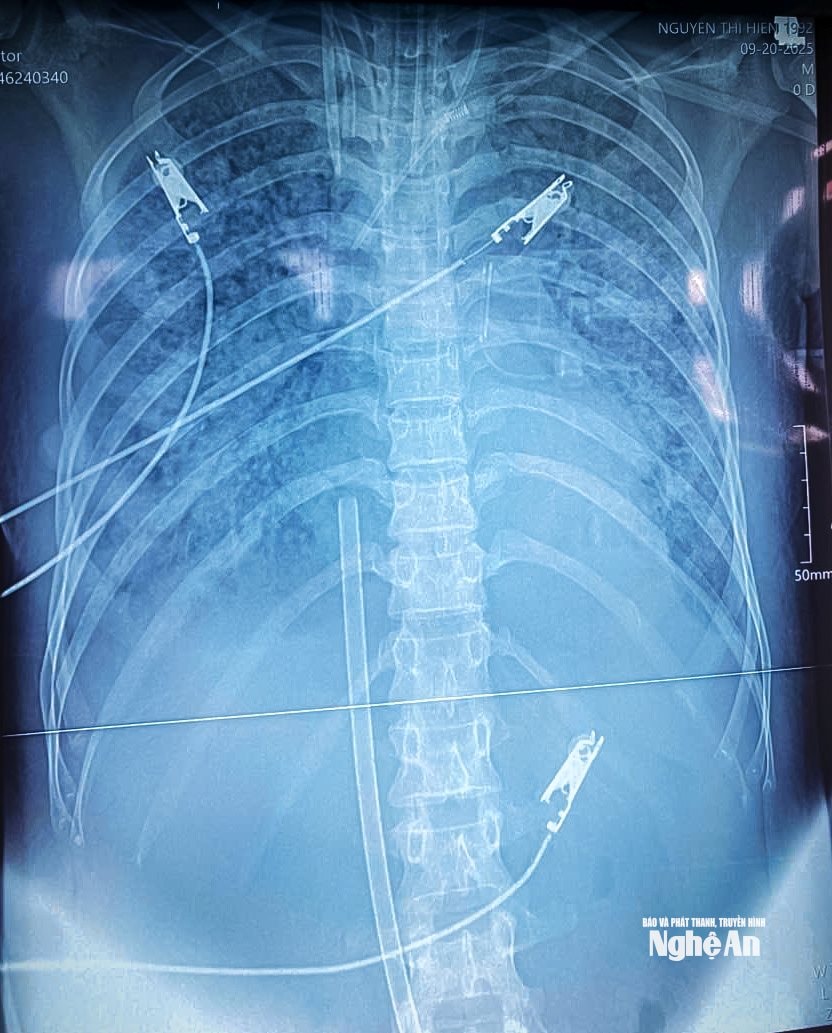

Пациентка НТХ (37 лет, провинция Нгеан) была доставлена в больницу членами семьи в состоянии острой дыхательной недостаточности, с учащенным и затрудненным дыханием, сатурацией кислорода в периферической крови (SpO2) всего 70% и многочисленными хрипами в обоих легких.

Несмотря на своевременное вмешательство, состояние пациента быстро ухудшилось: наблюдались изменения сознания и тяжелая дыхательная недостаточность, потребовавшая интубации и инвазивной механической вентиляции легких. Даже при оптимальной механической вентиляции в сочетании с тремя типами вазопрессоров и высокими дозами препаратов для кардиологической поддержки пациенту не удалось достичь целевого уровня оксигенации крови и артериального давления, что привело к очень высокому риску летального исхода.

Врачи отделения интенсивной терапии решили применить ЭКМО — метод искусственного кровообращения, считающийся «крайней мерой» в реанимации. Уникальность этого случая заключалась в том, что у пациента, несмотря на применение трех вазопрессоров и высокодозной кардиостимуляции, наблюдалось как низкое кровяное давление, так и тяжелая дыхательная недостаточность; следовательно, одной лишь ЭКМО было недостаточно. Врачи выбрали гибридную ЭКМО (ВАВ-ЭКМО) — комбинацию вено-венозной и вено-артериальной ЭКМО, обеспечивающую как дыхательную, так и циркуляторную поддержку.

Параллельно с применением VAV ECMO пациент также получал комплексное интенсивное лечение, включающее инвазивную механическую вентиляцию легких, непрерывную заместительную почечную терапию, гемодиализ с адсорбцией цитокинов, антикоагулянтную терапию, комбинированную и оптимизированную антибиотикотерапию на основе тестирования чувствительности к антибиотикам, профилактику язв, упражнения по респираторной реабилитации и комплексную нутритивную поддержку, что способствовало постепенной стабилизации его состояния здоровья.

К 7 октября жизненные показатели пациента стабилизировались, аппарат искусственной вентиляции легких был отключен, а эндотрахеальная трубка удалена. На 14-й день после начала ЭКМО параклинические показатели и клиническое состояние пациента значительно улучшились. Затем пациент был отключен от ЭКМО и возвращен в отделение интенсивной терапии. После 29 дней интенсивного лечения, 24 октября, пациент был выписан.